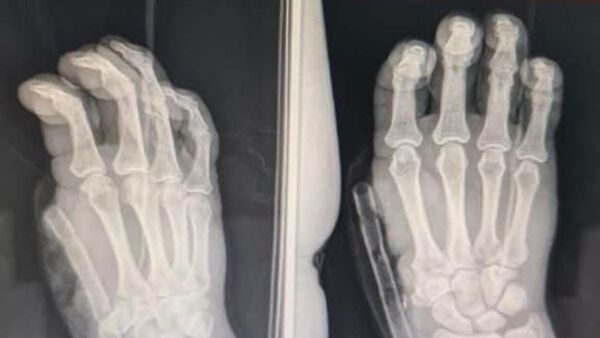

La increíble transformación de un dedo pulgar amputado

En IPS Central se logró extender el dedo índice de la mano. "Ahora está súper feliz", afirmó uno de los médicos traumatólogos. ...[Leer más]